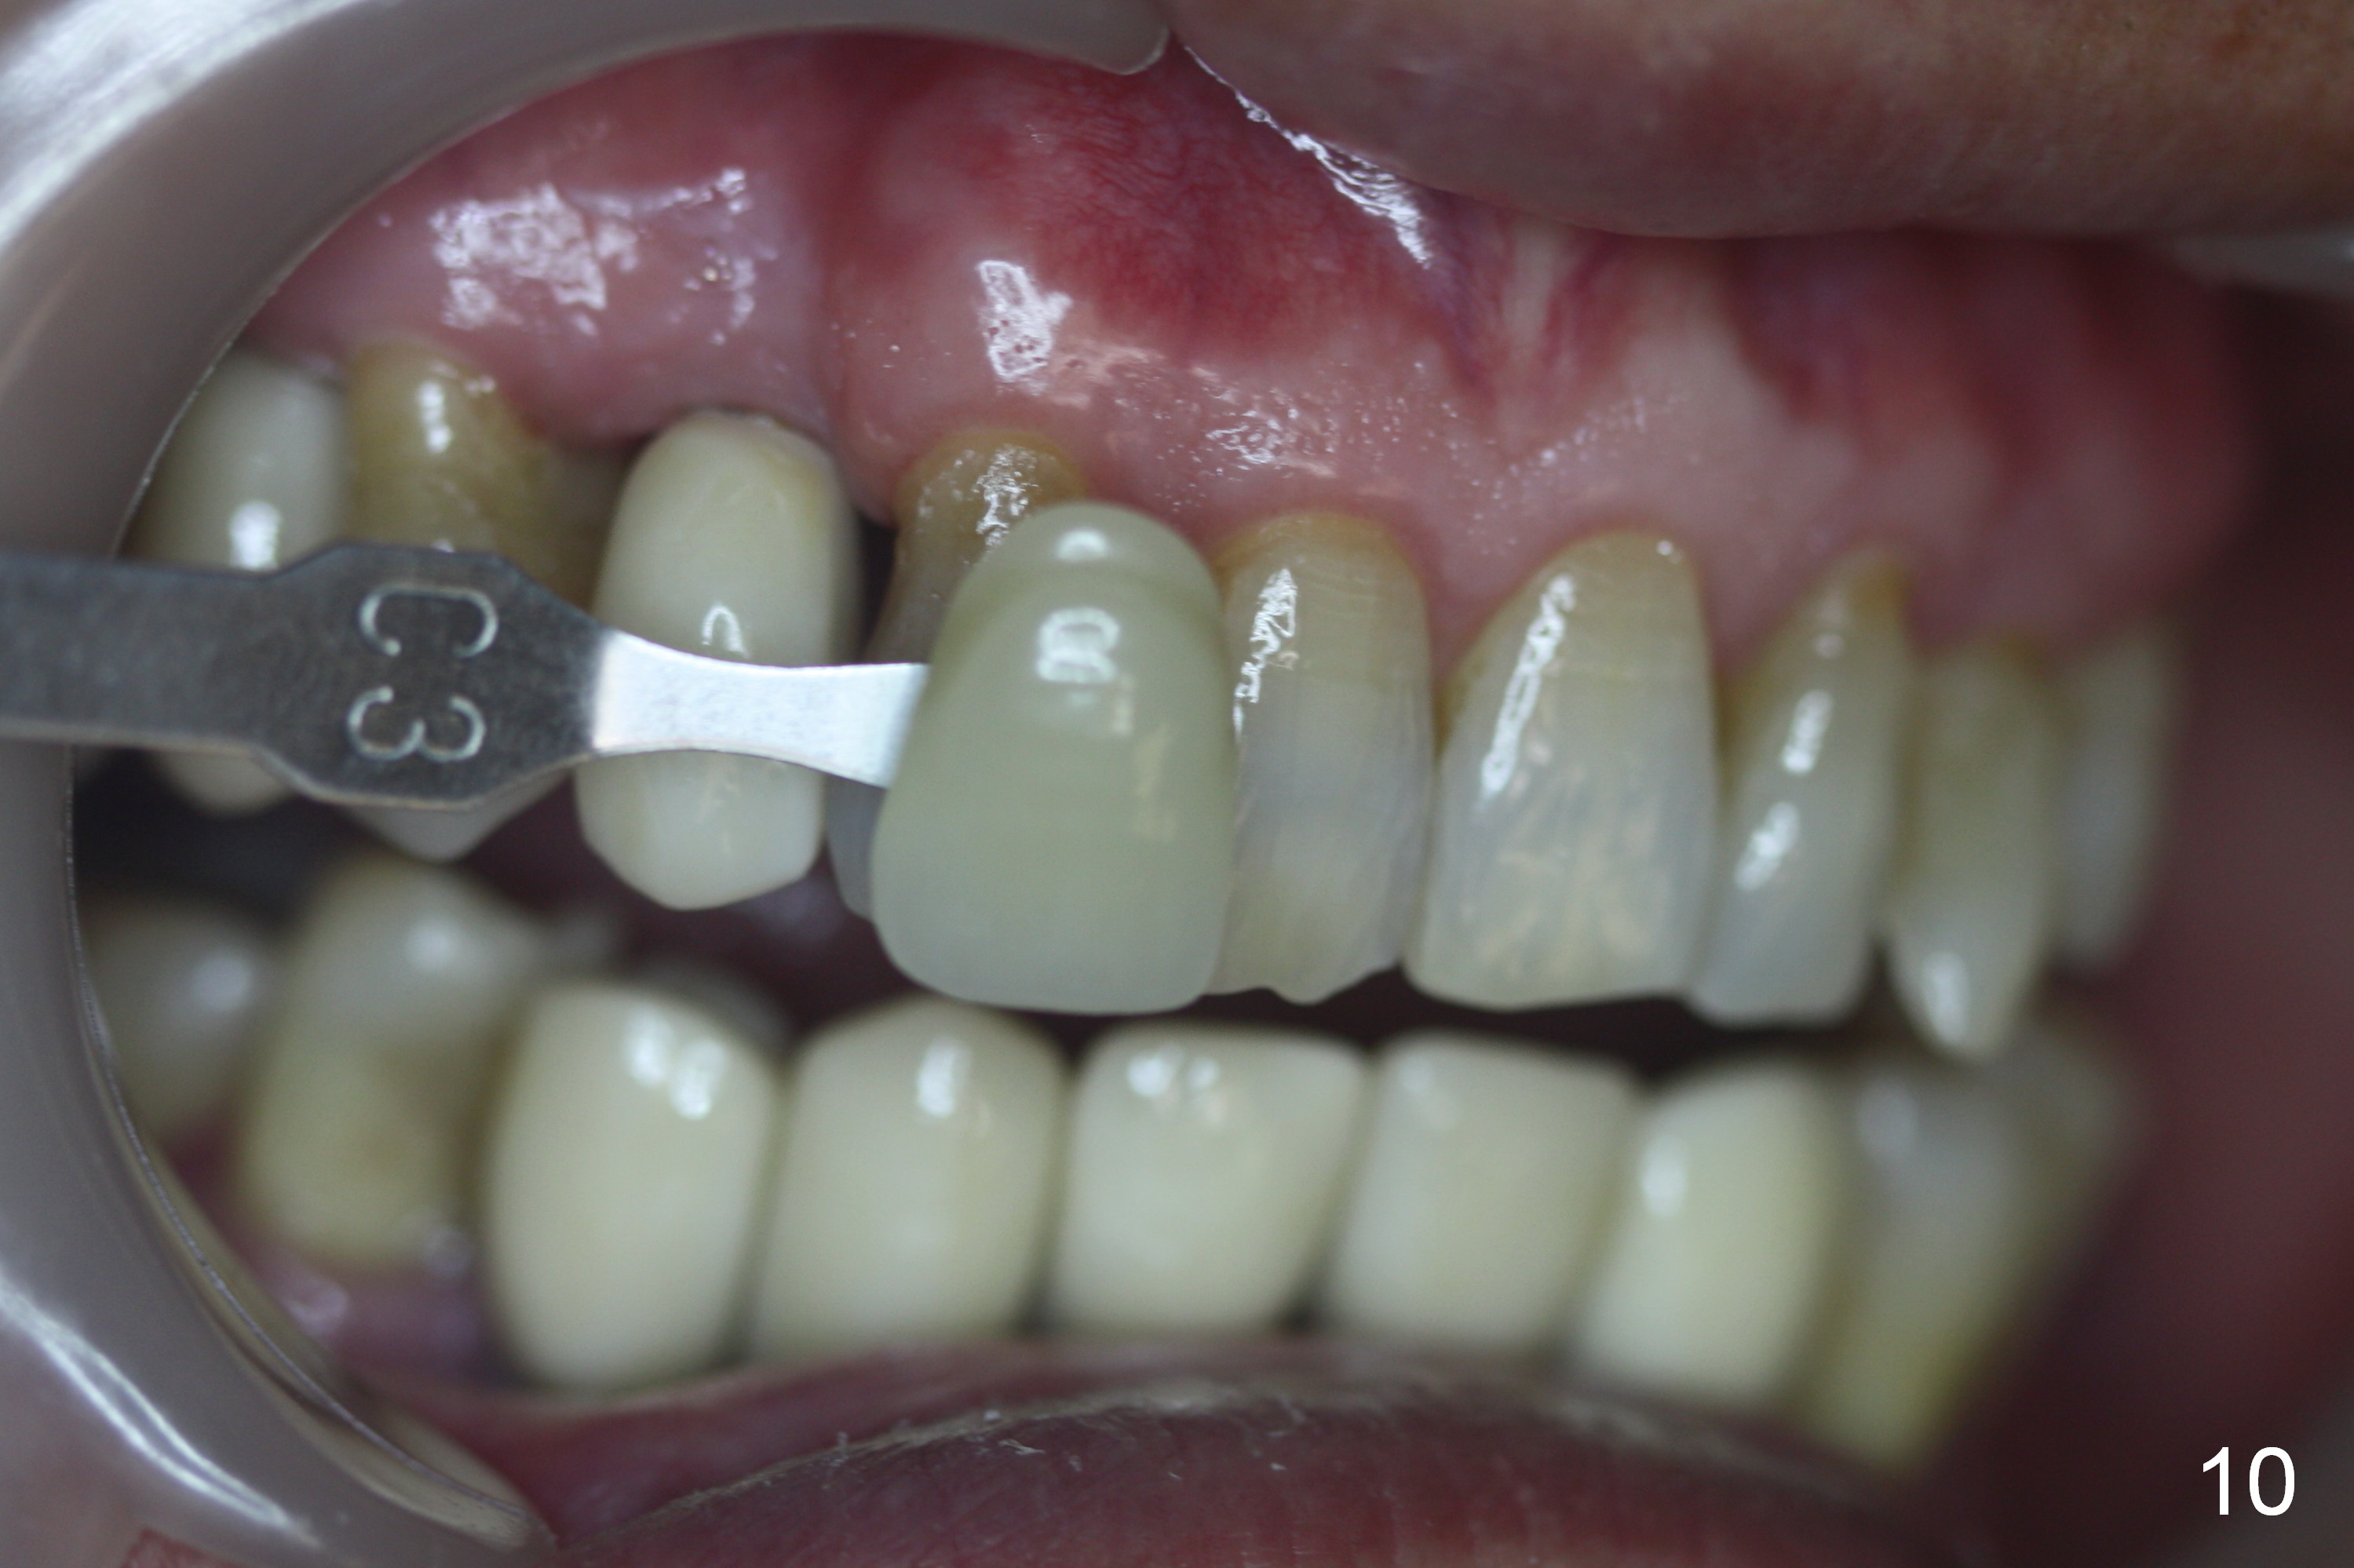

When the final crowns are seated, the shade is off. It appears that C3 is appropriate (Fig.10,11). Please make the crowns more transparent.